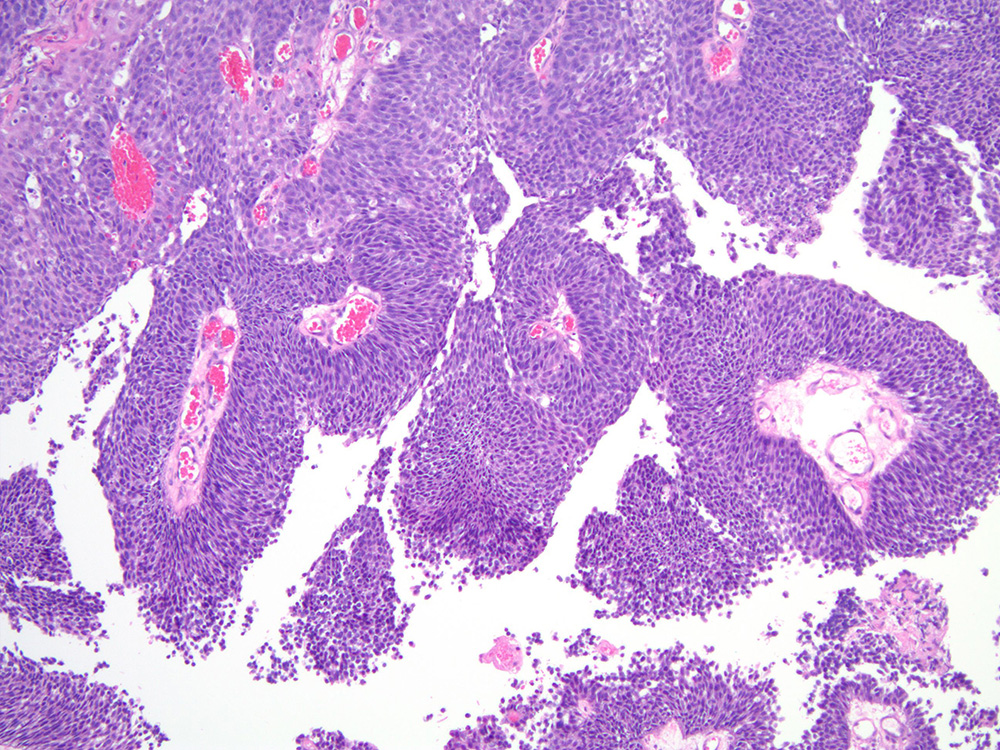

Bladder Papillary Lesions

Case ID: 458